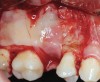

Fig 10. Small Schneiderian membrane perforation (arrow) during a standard lateral approach.

Figure 10